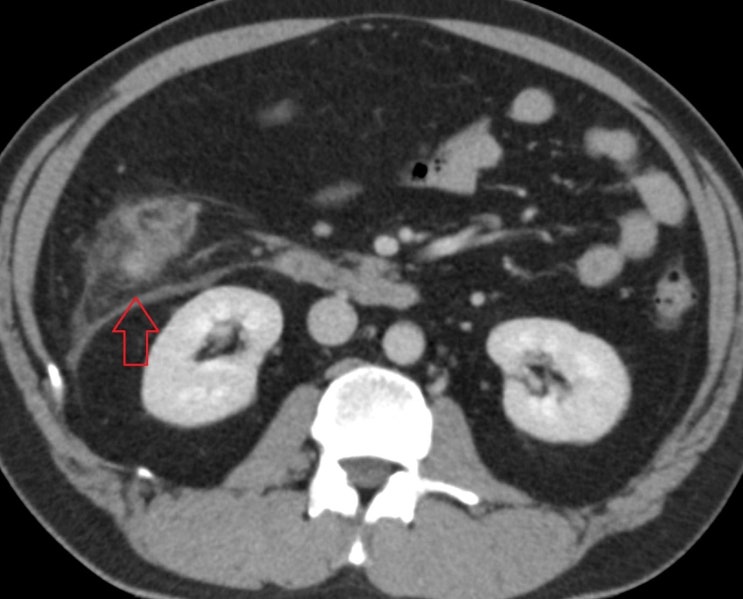

동일 증상으로 이상증상을 호소하여 좀더 세밀한 관찰을 위해 복부CT 검사를 시행하였습니다. 기본 피검사와 복부 X-ray에서는 특이 소견이 없었으나, CT에서 게실염 소견이 확인되었습니다.

복부CT에서 대장에 있는 게실 주변으로 염증 소견이 확인되었습니다. 게실염은 수술을 요하는 병은 아니나, 항생제를 써야 하는 질병으로 단순 장염과는 감별이 필요합니다.

• 복부CT: 대장 게실 주변 염증 소견 복부CT: 대장 게실 주변 염증 소견